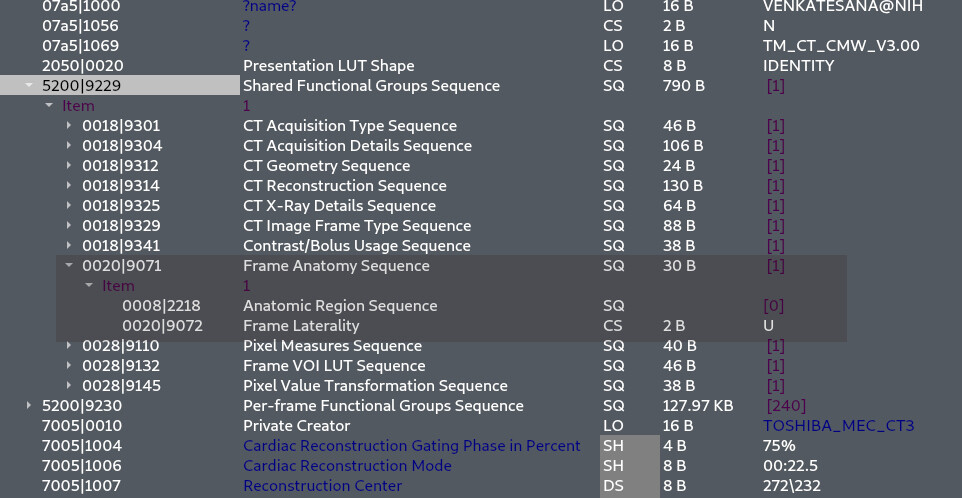

Enhance care with our medical Python Library Rt Dicom Monaco gallery of comprehensive galleries of therapeutic images. medically documenting photography, images, and pictures. designed to support medical professionals. Discover high-resolution Python Library Rt Dicom Monaco images optimized for various applications. Suitable for various applications including web design, social media, personal projects, and digital content creation All Python Library Rt Dicom Monaco images are available in high resolution with professional-grade quality, optimized for both digital and print applications, and include comprehensive metadata for easy organization and usage. Discover the perfect Python Library Rt Dicom Monaco images to enhance your visual communication needs. Our Python Library Rt Dicom Monaco database continuously expands with fresh, relevant content from skilled photographers. Instant download capabilities enable immediate access to chosen Python Library Rt Dicom Monaco images. Diverse style options within the Python Library Rt Dicom Monaco collection suit various aesthetic preferences. The Python Library Rt Dicom Monaco archive serves professionals, educators, and creatives across diverse industries. Regular updates keep the Python Library Rt Dicom Monaco collection current with contemporary trends and styles. Comprehensive tagging systems facilitate quick discovery of relevant Python Library Rt Dicom Monaco content. Time-saving browsing features help users locate ideal Python Library Rt Dicom Monaco images quickly.